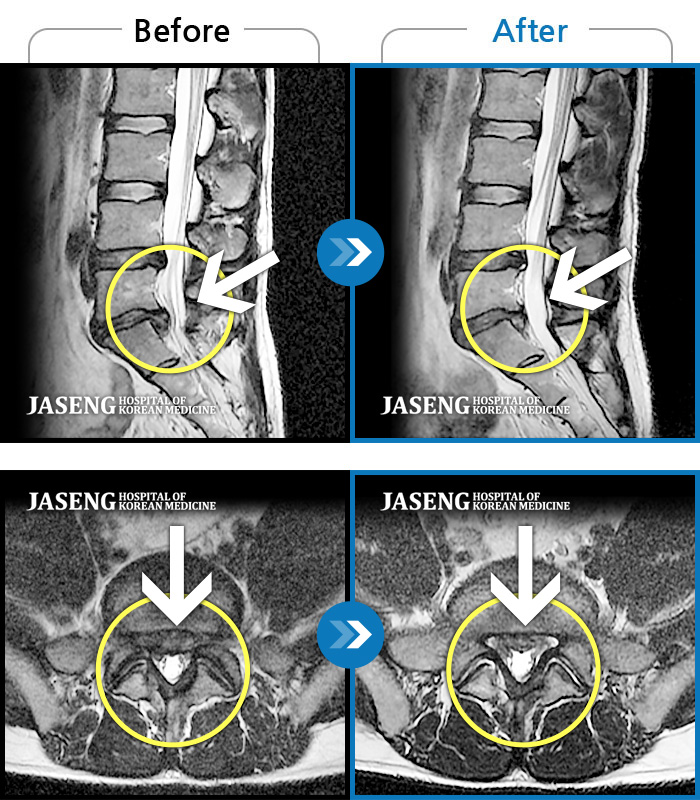

Before

After

환자에게 사전 동의를 받아 동일 조건에서 촬영되었습니다.

개인에 따라 치료 후 부작용이 발생할 수 있으니 의료진과 상담 후 치료를 진행하시기 바랍니다.

허리 골반 통증, 우측 다리가 뒤로 당김

좌측 엉덩이 통증과 함께 좌측 종아리 통증